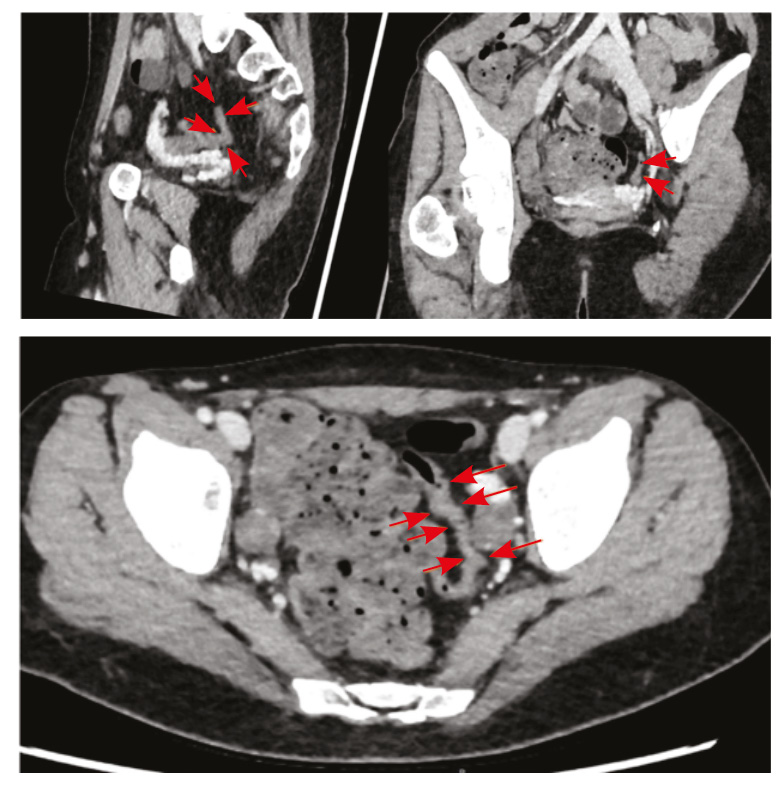

По результатам КТ органов брюшной полости с контрастным усилением, КТ- энтерографии определено утолщение стенки сигмовидной кишки до 5 мм на протяжении 60 мм, стенка без повышенного контрастирования (толщина стенки в остальных отделах не превышала нормы (2–3 мм), петли тонкого и отделы толстого кишечника расположены типично, стенки их с равномерным накоплением контрастного вещества, без достоверного наличия дополнительных образований, рельеф слизистой без отека, параколическая клетчатка не уплотнена, брыжеечные лимфатические узлы не увеличены. Заключение: КТ-признаки утолщения стенок сигмовидной кишки (поствоспалительные, постколитические изменения?), узелковая гиперплазия левого надпочечника (рис. 2).

Рис. 2. Компьютерная томографическая энтерография (30.03.2022). Стрелками указан измененный участок сигмовидной кишки: стенка утолщена до 5 мм на протяжении 60 мм, без повышенного контрастирования